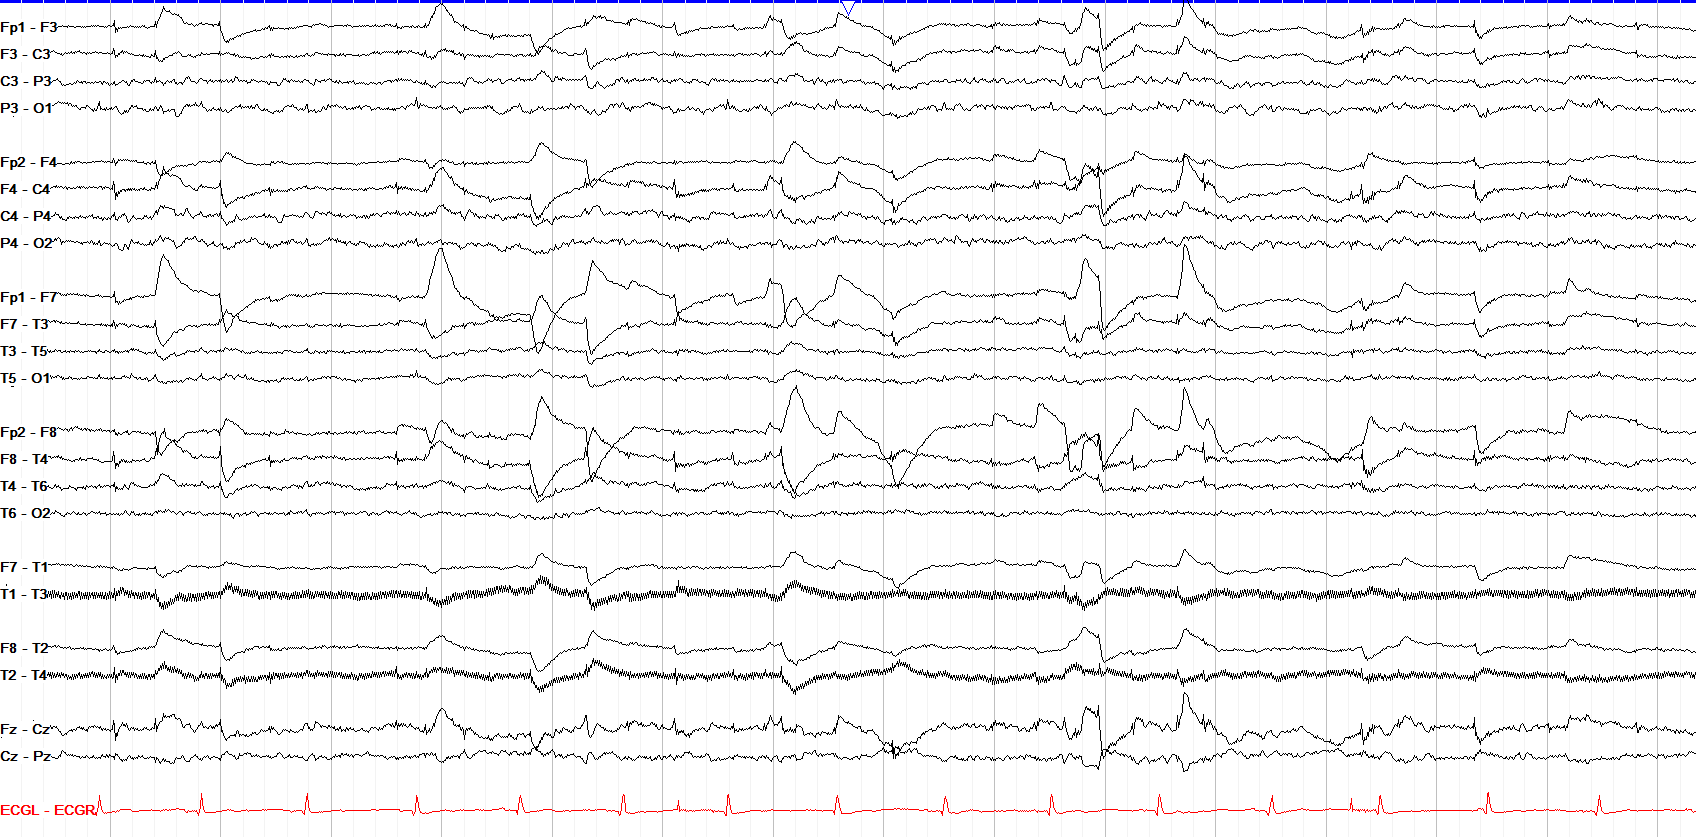

From eegatlas-online.com

rapid eye movement (REM) sleep Why Does Eye Move In Rem Sleep Web according to a new study by researchers at tel aviv university in israel, each flick of the eye that occurs during rem sleep. Web learn the fascinating science behind the rapid eye movements that occur during our dreams, and how they affect our memory. Web as the name implies, our eyes move in the rapid eye movement (rem) sleep. Why Does Eye Move In Rem Sleep.

From www.learningeeg.com

The Normal Asleep EEG Why Does Eye Move In Rem Sleep Web as the name implies, our eyes move in the rapid eye movement (rem) sleep stage. The name “rapid eye movement” comes from the observation that a person’s eyes move. Web learn the fascinating science behind the rapid eye movements that occur during our dreams, and how they affect our memory. Web according to a new study by researchers at. Why Does Eye Move In Rem Sleep.